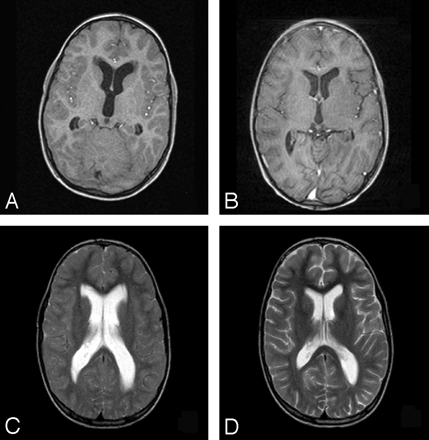

Periventricular lesions were detected and classified in irregular or smooth lesions (Fig 1), according to Fazekas et al.10 “Smooth delineation” was defined as having a smooth outline with normal-appearing white matter in all sections showing the PVWMH. Left and right PVWMH were considered separately. The classification of PVWMH was assessed in a consensus meeting by 3 of the authors (M.A.V.B., R.G., and A.S.). This was done for occipital and frontal periventricular lesions separately by using T2-weighted, proton density (PD), and FLAIR images. On T1-weighted images, the presence of periventricular hypointense lesions was assessed (Fig 2). They were defined as lesions with signal intensities on T1-weighted images lower than those of the surrounding white matter but higher than those of CSF.

Example of a PVWMH with the characteristic high signal intensity on a T2-weighted image (A) with a low signal intensity on a T1-weighted image (B) (arrow).

The periventricular hypointensities on the T1-weighted images all had smooth linings, regardless of the lining of the WMH on T2-weighted images. In Table 2, the proportions of PVWMH with a hypointense appearance on T1-weighted images are shown. Most of the frontal PVWMH had a low signal intensity on T1-weighted images (76%), whereas only 35% of occipital PVWMH were hypointense on T1-weighted images. No correlation was observed between the presence of hypointense signal intensity on T1-weighted and irregularity of the PVWMH on T2-weighted images. In PVWMH with a low signal intensity on T1-weighted images, the area with a hypointense signal intensity was invariably smaller than the area with a high signal intensity on T2-weighted images.

PVWMH in the frontal location more often showed low signal intensity on T1-weighted images than those located occipitally, corroborating the suggestion of differences in tissue composition between these 2 locations based on our MTI analysis. These hypointense areas may partly be explained by more severe tissue destruction in this location, but the specific shape of the hypointense areas around the frontal horns and the relationship of the hypointense areas with the areas with high signal intensity on T2-weighted images rather suggest a different pathogenesis. The frontal hypointense areas invariably had the appearance of smoothly delineated frontal caps, irrespective of the delineation of the same lesions on T2-weighted images (Fig 2). Often the frontal hypointense areas were smaller than the hyperintense areas in the same location and in the same subjects (Fig 2). The morphologic similarity between the frontal periventricular hypointense lesions and the frontal hyperintense caps that are prevalent in most adults suggests that 1) these lesions are based on the same etiology and 2) this etiology differs from that of the occipital and larger irregular frontal PVWMH. On the basis of our observations, we hypothesize that frontal PVWMH are partly caused by increased interstitial fluid accumulation and partly by ischemia, whereas in the development of occipital and large irregular frontal PVWMH, there is less influence of interstitial fluid dynamics. This hypothesis is supported by observations from Fazekas et al,10 who demonstrated that irregular PVWMH on MR imaging correlated with more severe ischemic changes on histology than smooth PVWMH did.